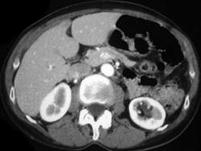

问题 女,28岁,请根据所示图像,选择最可能诊断 ( )

选项 A、左侧高密度肾囊肿 B、左侧单纯性肾囊肿合并感染 C、左侧单纯性肾囊肿 D、左侧钙化性肾囊肿 E、左侧肾癌

答案 A